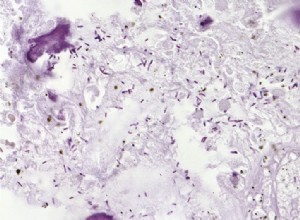

Bactéries du sol contre le cancer : une thérapie innovante testée sur chiens et humains